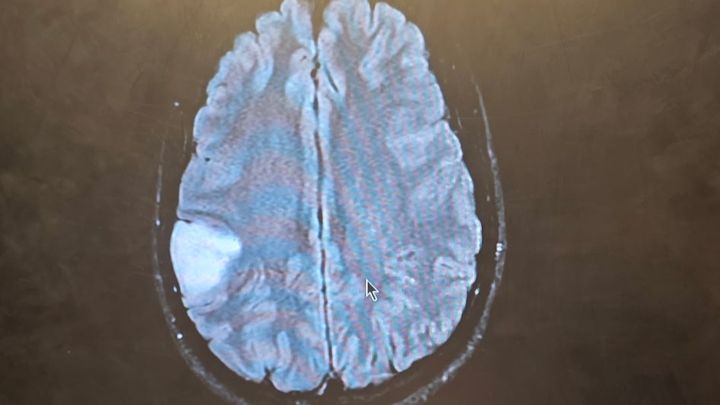

My 32-year-old son Tanner recently experienced a terrifying health crisis. He suddenly lost feeling on the left side of his body, and his wife rushed him to the nearest hospital. After being transferred by ambulance to St. Cloud, doctors performed an MRI and discovered that Tanner had not suffered a stroke, but a seizure. The MRI revealed a mass on his brain the size of a golf ball, pressing on the area that controls his motor skills.